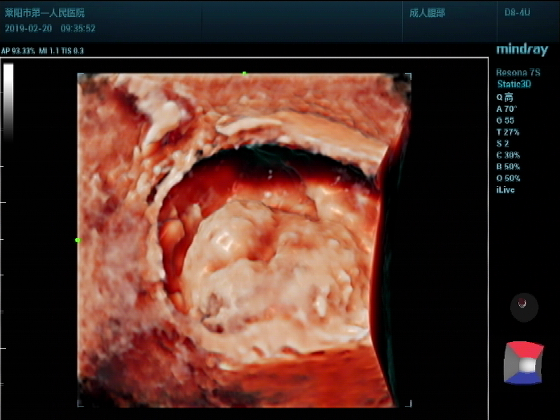

超声入门贴987--前列腺增大并膀胱结石(三维图)

男,75岁超声可见:前列腺明显增大,以内腺增大为主,内腺向膀胱内突入约2.17CM.实质回声尚均匀。膀胱腔内见弧线状强回声团,后伴声影,位置活动。

三维成像:前列腺向膀胱腔内呈“唇样“隆起,表面光滑。膀胱腔内结石团呈”蚕豆样“

这种三维立体图像主要观察异常超声立体形状,大小测量更准确,同时与邻近输尿管入口关系,看是否有压迫堵塞,以及与邻近膀胱壁是否黏连,进而指导临床下一步选择治疗方案。